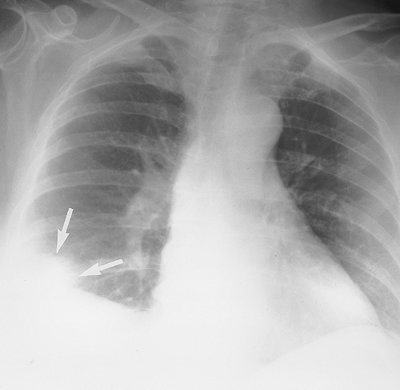

Pulmonary infarction results in airspace opacities that are usually multifocal and predominantly in the lower lungs. They usually appear within 12 to 24 hours after the embolic event. The opacities are classically peripheral, with a triangular or rounded shape (thus the term Hampton hump), and they are always in contact with the pleural surfaces (Figs. 17-23 and 17-24). The apex of the opacity is directed toward the lung hilum. Occasionally, lobar opacity resembling pneumonia can occur. Air bronchograms are rarely present. It is important to note that the opacities can represent a combination of pulmonary hemorrhage and atelectasis without infarction, in which case clearing occurs within a week. Infarction takes several months to resolve, often with residual scarring (Fig. 17-25). As infarcts resolve, they melt away "like an ice cube" (giving rise

FIGURE 17-23. Pulmonary infarction. PA chest radiograph of a 68-year-old woman with acute shortness of breath shows a pleural-based, rounded opacity at the right costophrenic angle (Hampton hump; arrows), representing an acute parenchymal infarct. There is elevation of the right hemidiaphragm from atelectasis and subpulmonic effusion.